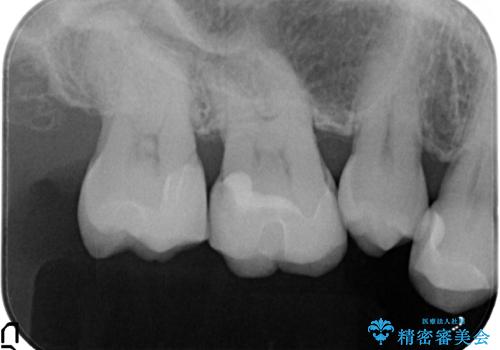

- つめものが欠けたとのことで、来院された患者様です。

レントゲンから虫歯が深いことが予想されたため、神経の処置が必要になる可能性を説明した上で、

白いもの希望とのことで、セラミックインレー修復を行う方針をたてました。

レントゲンから、虫歯が深いことが予想されたため、ラバーダムを使用して虫歯治療を行いました。

幸い、そこまで虫歯は深くなく、神経の処置は必要なかったため、

予定通り、セラミックインレー修復を行いました。